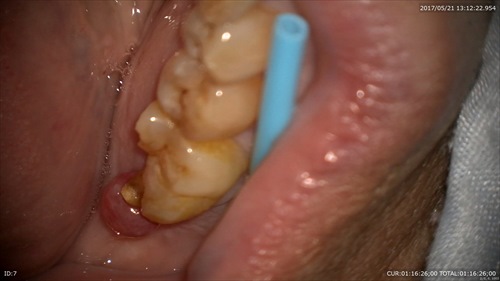

こんな状態でした。一番奥に膿の塊が見えます。歯周病と混在している病巣でぼくらの業界では治すのは難しいとされている1つの状態です。

根管から膿が。。。。